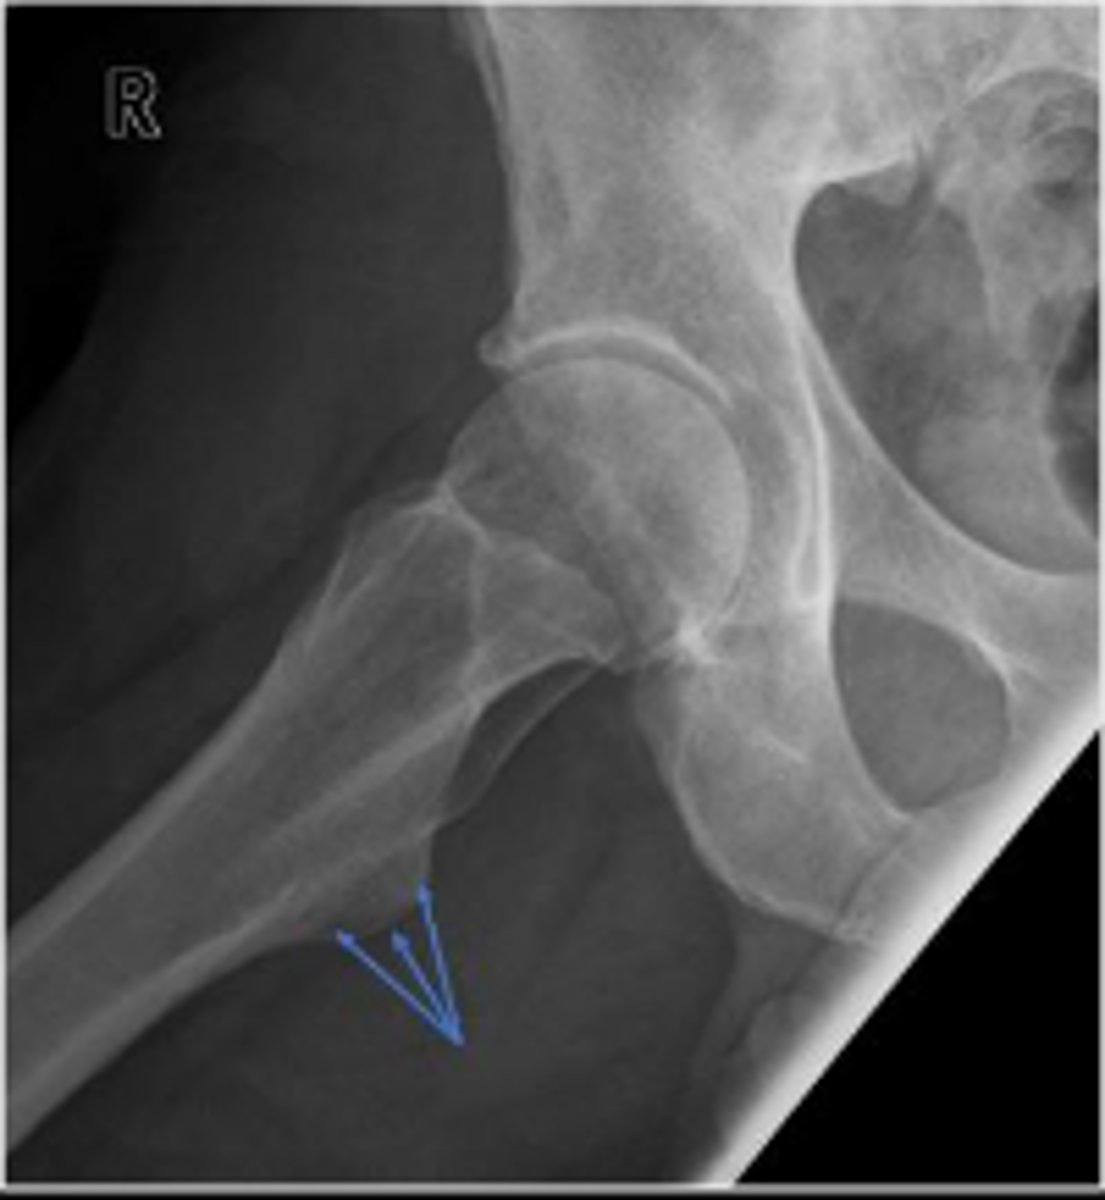

Right frog-leg hip

What is the name of the radiographic view?

Lesser trochanter of the right femur

What are the arrows pointing to?

Greater trochanter of the right femur

Intertrochanteric line of the right femur

Right ischial tuberosity